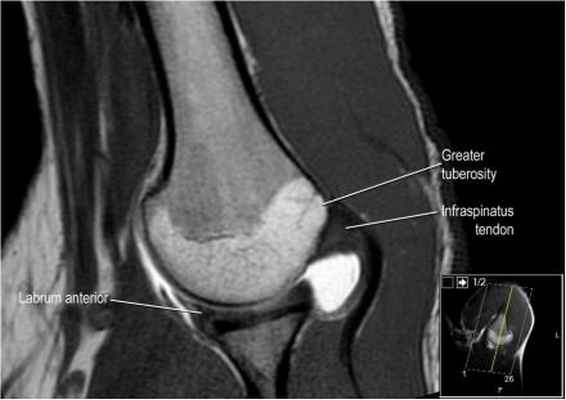

а бРис. 1. МР-артрография. МР-томограммы ПС: а – корональная плоскость, T1 TSE; б,в – аксиальная плоскость T1 TSE, FS T1 TSE

Протоколы нативного МР-исследования и МРА плечевого сустава включали получение трех взаимно перпендикулярных проекций (косой коронарной, косой сагиттальной и аксиальной). Нативное исследование проводилось с использованием следующих импульсных последовательностей: TSE PD SPAIR – изображения, взвешенные по протонной плотности, с эффектом подавления сигнала от жировой ткани; TSE_T1W-Т1 взвешенном изображении (ВИ) в режиме турбо-спин эхо; FFE_T2W-Т2 ВИ в режиме градиентного эхо (табл.1). МРА проводили в режиме TSE_T1W, а также с использования эффекта жироподавления – TSE_T1W SPIR (табл.2, рис.1). Исследование проводилось через 15 минут после введения контраста и выполнения пациентом маятникообразных движений верхней конечностью.

Изображение задних отделов плечевого сустава.

Отображены надостная, подостная и малая круглая мышцы и их сухожилия. Все они прикрепляются к большому бугорку плечевой кости. Сухожилия и мышцы манжеты вращателей участвуют в стабилизации плечевого сустава во время движения. Без манжеты вращателей головка плечевой кости частично сместилась бы из суставной впадины, уменьшив силу отведения дельтовидной мышцы (мышцы вращательной манжеты координирует усилия дельтовидной мышцы). Повреждение манжеты вращателей может привести к смещению головки плечевой кости кверху, в результате вызвая высокое стояние головки плечевой кости.